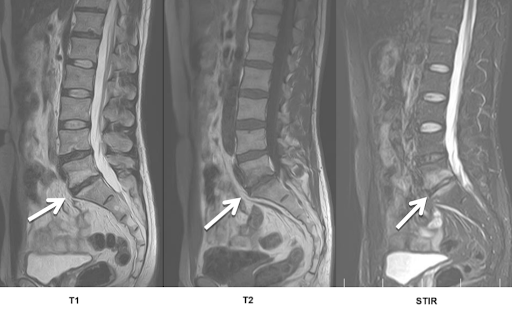

Изменение по типу modic 1